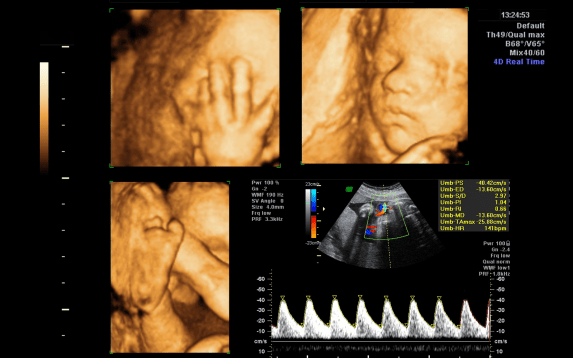

An anomaly scan is a detailed ultrasound performed during pregnancy to check the baby’s growth and detect any birth defects. It is usually done between 18 and 22 weeks. This mid-pregnancy scan helps assess the baby’s organs, spine, limbs, brain, and heart. Since it provides a clear picture of fetal development, it is also known as a level-II or mid-trimester ultrasound.

The anomaly scan plays a crucial role in ensuring the baby’s health. It helps identify structural abnormalities such as heart defects, cleft lip, kidney issues, or skeletal problems. Early detection gives doctors time to plan further care and treatment if needed. Moreover, this scan confirms placental position and amniotic fluid levels, which are essential for a safe pregnancy.

At Isha IVF Centre, specialists use high-resolution ultrasound machines for every anomaly scan. The centre’s fetal medicine experts carefully examine each part of the baby to ensure accurate results. Along with 2D imaging, 3D and 4D scans give clearer visuals of the baby’s movements and features. With modern technology and expert care, Isha IVF Centre ensures safe, detailed, and precise fetal evaluations.